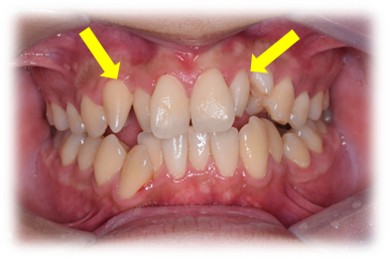

矮小歯(円錐歯、栓状歯)

上顎の側切歯によく見られます。歯が、小さく・細くなっている状態です。

矯正治療で並べると、上下左右の歯の大きさとのバランスが問題になります。上下歯列の真ん中が一致しきれなかったり、かみ合わせにわずかなずれが生じることがあります。

事前あるいは矯正治療中にこのままの大きさでよいのか?という事を話し合っておく必要があり、歯の大きさをかえる場合は、それを考慮した治療方針にする必要があります。